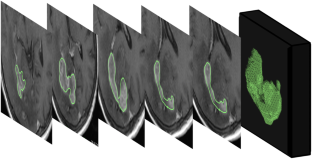

A total of 142 patients with HGG were included in the study. IDH1 mutation was present in 48 of 142 HGG (33.8%). Patients were randomly divided into the training cohort (n = 96) and the validation cohort (n = 46). Texture features were extracted via regions of interest on axial T2WI FLAIR, post-contrast T1WI, and ADC maps covering the whole volume of the tumors. The training cohort was used to train the random forest classifier, and the diagnostic performance of the pre-trained model was tested on the validation cohort.

Fig. 1